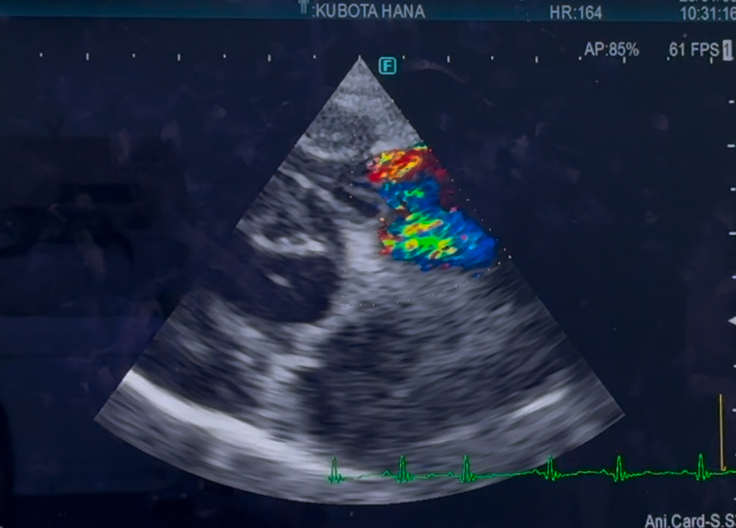

手術した、左心の方は

変わらず逆流は、あるものの

悪化はみられず、変わりなしでした

右心の、三尖弁の逆流は

少し、増えているかも…とのことでしたが

多少の、増減はあるものだと言うことと

数値より、症状があるかどうかにより

対処療法を、していくので

今現在は、咳もほとんどなく

症状は、みられないので

経過見となりました…